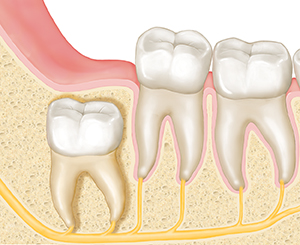

Wisdom teeth that can’t fully break through the gum (erupt) are called impacted. These teeth can grow in almost any direction, including:

Straight up, but without room to erupt into a healthy position

Angled away from the other teeth

Parallel to the gumline

Angled in toward the other teeth

| Straight upward. |

| Parallel to the gumline. |